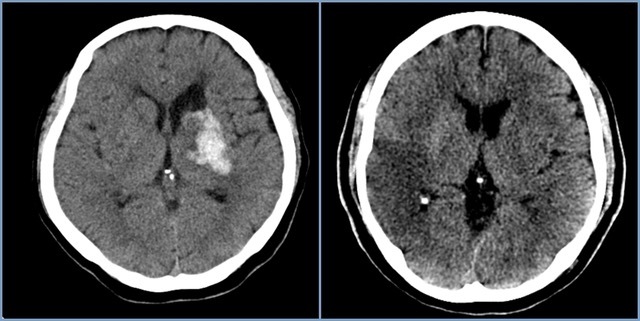

뇌경색은 병에 걸려 후 얼마나 빨리 치료를 착수하는지에 따라 병의 증세가 결심되기도 합니다. 증상이 발생하면 아주많이 빨리 병원을 가서 초급성기 치료를 받아야합니다. 급성기 치료 후에는 이유가 되는 것에 따라 재발 방지를 위한 치료를 하게 되며 후유증에 대한 재활치료도 가능한 한 빨리 실행하는는게게 좋바람직해요. 증상이 처음 나타난 후 4~5시간이 경과하지 않으신다면 주사 제제를 통한 혈전용해술을 시도해 볼 수 있어요. 그리고 24시간이 경과하지 않았고 대뇌혈관이 막힌 것을 확인했으면 막힌 혈관에 대하여서 스텐트 투여술과 같은 기계적 재개통술을 시도할 수 있습니다.

뇌경색 후유증은 제대로 걷지 못하며, 말을 잘 못하였거나, 나의 의지와는 다르게 출현하는 문제점들이 일어날 있다고 합니다. 그렇기에 뇌경색 초기증상이 발견될 시 날쌔게 조치를 해야 후유증이 희박합니다 뇌경색이 오면 후유증이 남는 것이 기본이며 일주일 안으로 나타나게 된다고 해요. 이 기간이 지나도 병의 증세가 없다고 하나 서서히 회복이 되는 단계에 있다고 보시면 되기도 합니다 뇌경색 후유증은 3개월에서 6개월 사이에 서서히 회복 될 수 있습니다. 치료가 늦어져서 뇌경색 후유증이 절박하게 자리잡게 된다면 일상생활이 어려울 정도로 사람의 몸에 이상이 있는 상태가 지켜질 수 있어요.